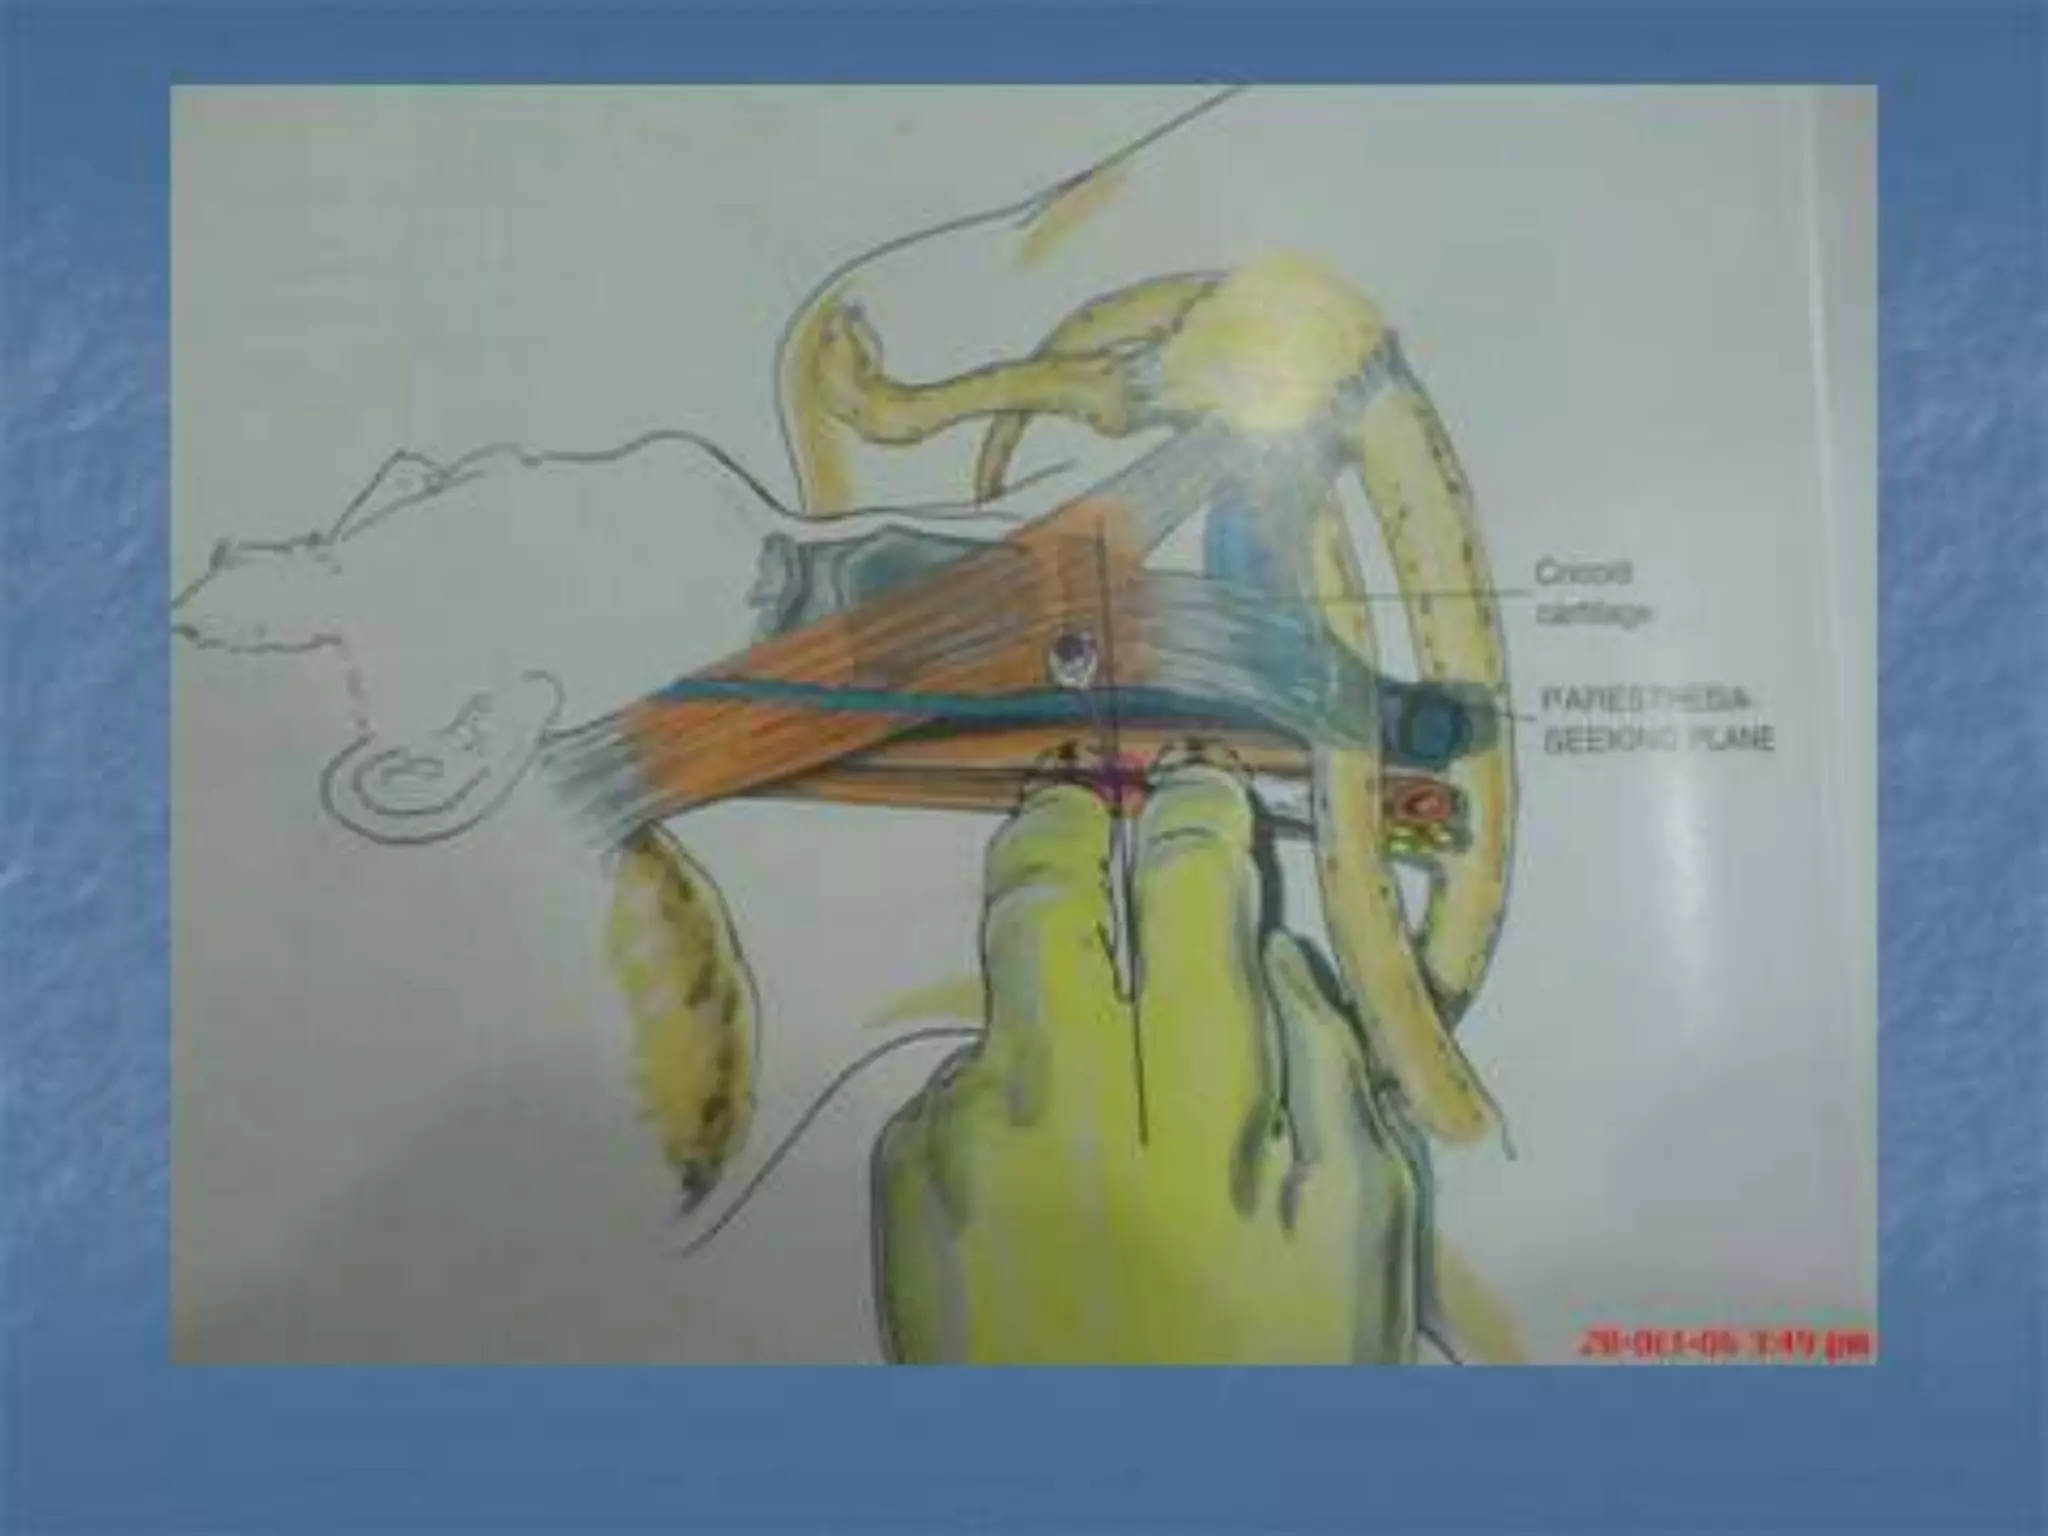

This document provides an overview of brachial plexus anatomy and techniques for brachial plexus nerve blocks. It begins with a description of the brachial plexus formation from cervical and thoracic nerve roots and its branching pattern. Four main approaches for brachial plexus nerve blocks are described: interscalene, supraclavicular, infraclavicular, and axillary. Details are provided on the anatomy and techniques for performing interscalene and supraclavicular brachial plexus blocks. Ultrasound guidance is discussed as an advancement which allows real-time visualization of needle and nerve. Complications are also summarized.